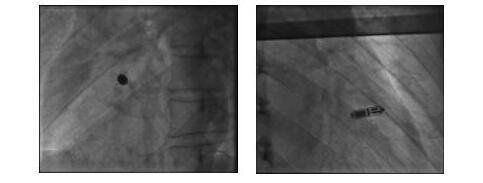

中新网黑龙江新闻6月5日电(齐魏依)形如一粒胶囊,重量不到2g,电池容量大,预计寿命最长可达12年。如此迷你的一枚心脏起搏器,却可以给患者一家人以重生的希望。近日,哈医大四院心内科肖模超教授带领团队成功为一名患者植入国际领先的Micra无导线起搏器。60岁的金大爷本该在家中享受天伦之乐,可他却仍是一家人的顶梁柱、主心骨,照顾着三个卧病在床的病人:金大爷的父母已近九十岁高龄,老伴也患有脑出血,都瘫痪在床,每天的...